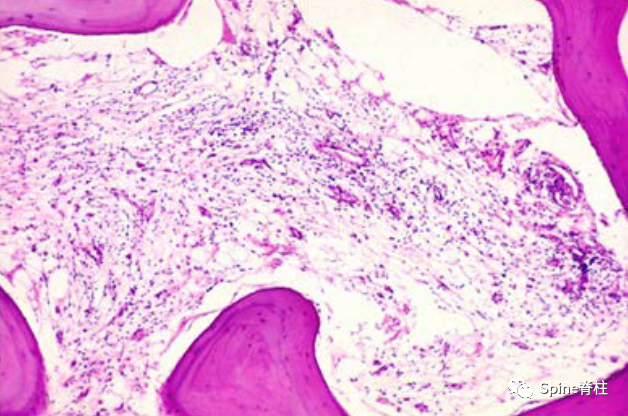

图3.MC-2组织学H&E染色,骨髓间隙脂肪替代,在T1加权图像上显示高信号